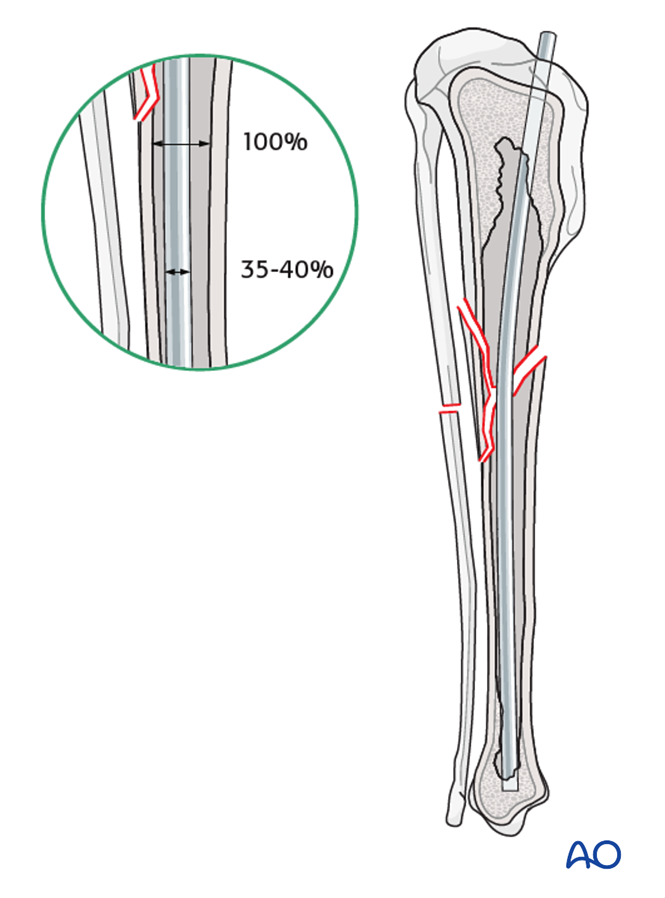

Plate and rod for One large reducible wedge in the tibial diaphysis

Plate and rod for Several reducible wedges in the tibial diaphysis

Plate and rod for Complex with reducible wedges in the tibial diaphysis

Plate and rod for Complex with nonreducible wedges in the tibial diaphysis

Plate and rod for Nonreducible wedges in the tibial diaphysis